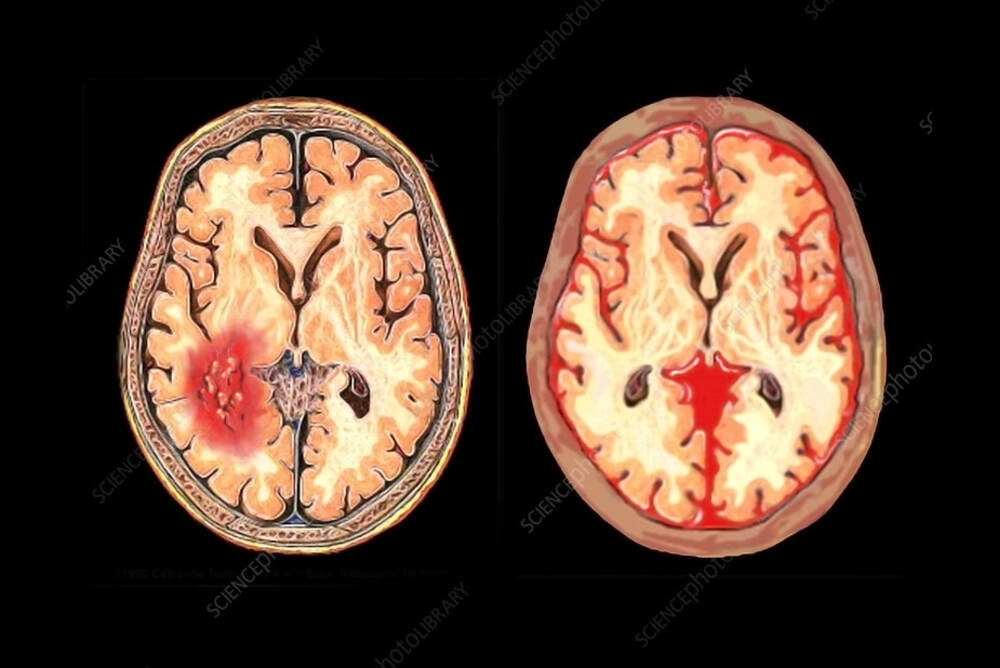

Vasospasm can be a very serious and frequent complication that may be seen following a subarachnoid hemorrhage (SAH). It's the sudden and involuntary shrinking (constriction) in cerebral blood vessels. The narrowing significantly reduces circulation of blood towards the crucial regions of the brain. This results in and thereby denying the brain being denied oxygen and nutrients. This could result in cerebral ischemia or a stroke, which could result in additional brain injury that goes in addition to the first bleeding. Vasospasm typically manifests in an exact timeframe, which is generally between days 3-14 following the hemorrhage. It is an essential aspect to consider in SAH treatment because it is an important cause of death and morbidity in patients who can recover from the initial hemorrhage. A blood vessel in the subarachnoid artery triggers an inflammation response, which irritates the walls of the vessels, increasing the possibility of developing this ailment.

The main reason for vasospasms is an underlying degrading of blood vessels in the subarachnoid space following hemorrhage. As blood clots dissolve they release inflammatory chemicals and other products such as the oxyhemoglobin. These chemicals trigger a chain of events which result in chronic inflammation, irritation, and eventually the continuous contracting of the smooth muscles in the arterial walls. This results in vasospasm.

- The location of blood Clots that are located close to major arteries in the middle of the brain (like that of the Circle of Willis) poses a higher risk.